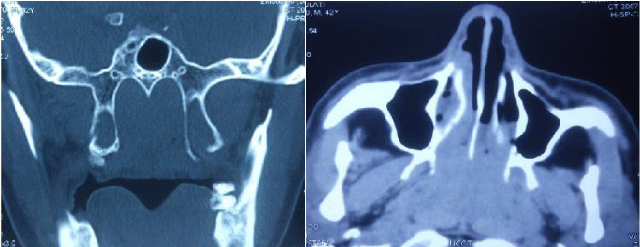

A 45 year old male presented to the ENT OPD, Lok Nayak Hospital, with complaints of nasal obstruction, snoring and repeated awakening at night due to apnea spells. On detailed history, it was found that patient was a chronic smoker for past 25 years. On examination, nasal endoscopy revealed a pale lobulated mass in the nasopharynx (Figure 1). Contrast enhanced CT scan showed a non-enhancing mass in the nasopharynx, extending upto bilateral nasal cavity, suggestive of adenoid hypertrophy (Figure 2). Nasal endoscopic biopsy was done which was suggestive of lymphoid hyperplasia. The patient was managed conservatively for 3 months with steroid nasal spray. However, there was no improvement in the symptoms and patient was planned for surgery. Transnasal endoscopic powered adenoidectomy was done under general anesthesia. Post-operative biopsy report was suggestive of adenoid hyperplasia. Adenoidectomy resulted in resolution of symptoms and immediate improvement in sleep. Topical steroid nasal spray was continued for one year postoperatively. After one year follow up, the patient was asymptomatic. There was no residual tissue in the nasopharynx or any recurrence.

Figure 1:

Figure 2:

A 35 year old male presented with bilateral chronic otitis media with mucosal disease. Even after tympanoplasty with cortical mastoidectomy, patient had persistent ear discharge. There was only temporary relief of symptoms and an underlying pathology was sought for. Nasal endoscopy revealed a lobulated mass in the nasopharynx. Contrast enhanced CT scan indicated a non-enhancing mass in the nasopharynx. Nasal endoscopic biopsy was done and histopathology report was suggestive of hypertrophied lymphoid tissue. Transnasal endoscopic powered adenoidectomy was done under general anesthesia. After a few months of surgery, the ear remained dry. Successful revision tympanoplasty was performed after 6 months. After one year follow up the patient was asymptomatic. Following surgery, there were no progress in the adenoid hyperplasia and related symptoms.